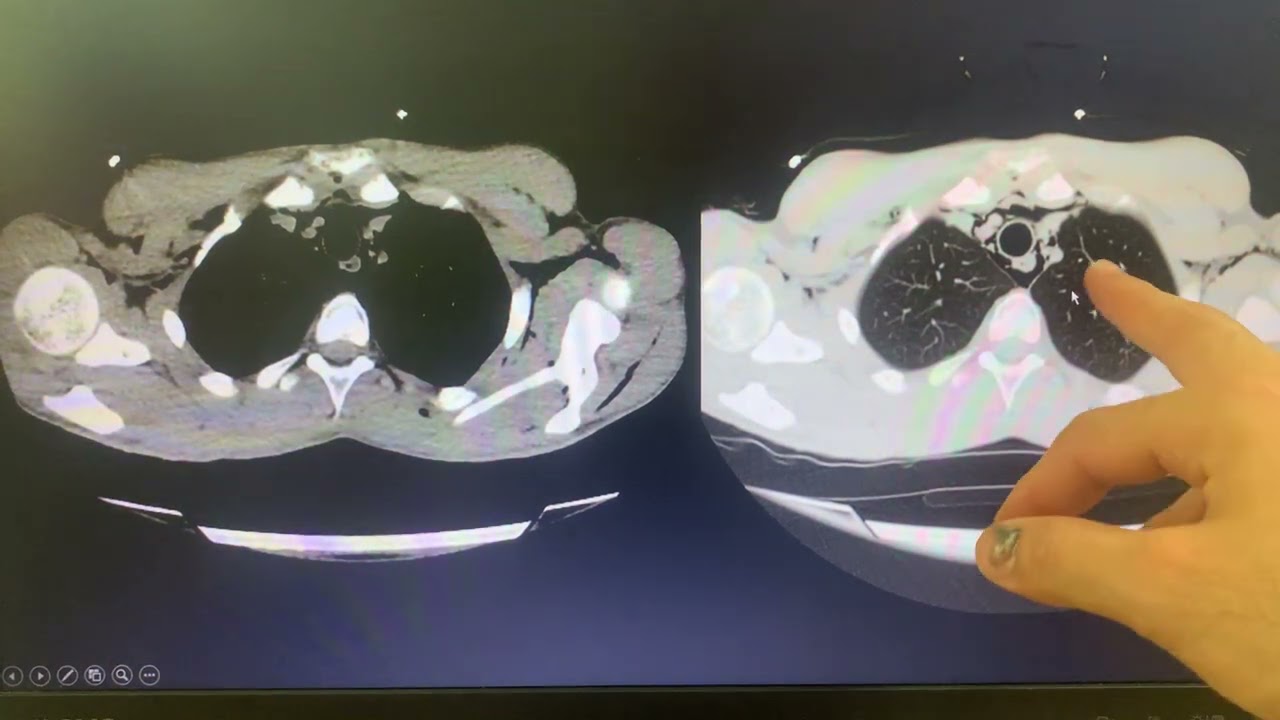

"Acil Serviste BT/Direkt Grafi Değerlendirme"

Dr. Öğr. Üyesi Ömer ÇANACIK

DEÜ Tıp Fak. Acil Tıp Anabilim Dalı